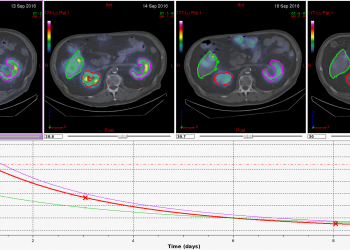

PLANET® Dose

“PLANET® Dose has been a pioneer in different types of treatment, including 90Y-SIRT liver and 177Lu therapies, the tool is largely used in our team and everyone can benefit: interventional radiologists, pharmacists, nuclear physicians and physicists. … CE marked, DOSIsoft was one of the first to offer personalized 3D dosimetry … For us, it’s now an indispensable clinical tool … and a real advance in ensuring optimal quality in the treatment of our cancer patients.”